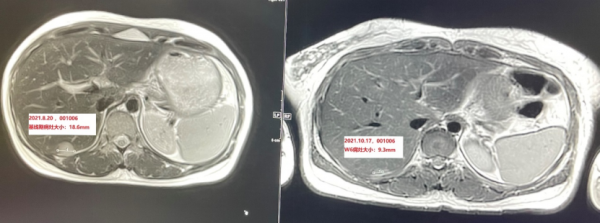

病例1患者被診斷為未分化非角化性並多發骨轉移晚期鼻咽癌,行誘導化療和根治性放療失敗後,接受一線治療鉑類聯合5-FU(PF方案)6個療程,卡培他濱4個療程,二線接受帕博利珠單抗治療持續近三年多,疾病進展後入組MRG003Ⅱ期臨床試驗,接受MRG003治療僅2次(6周),靶病灶直徑總和縮小31.6%,療效評估PR(圖1)。

圖一治療前(左上:肝S6段轉移病灶;左下:肝S8段轉移病灶)及治療後(右上:肝S6段轉移病灶;右下:肝S8段轉移病灶)病灶變化